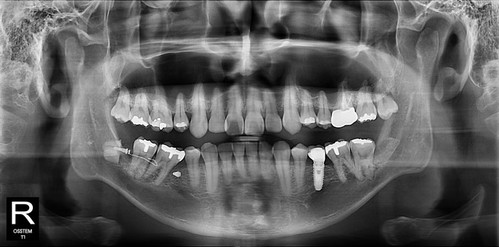

발치 후 오른쪽도 같은 방법으로 뽑고 싶다고...

역시 신경손상가능성을 최소화한 후

깔끔하게 발치완료~